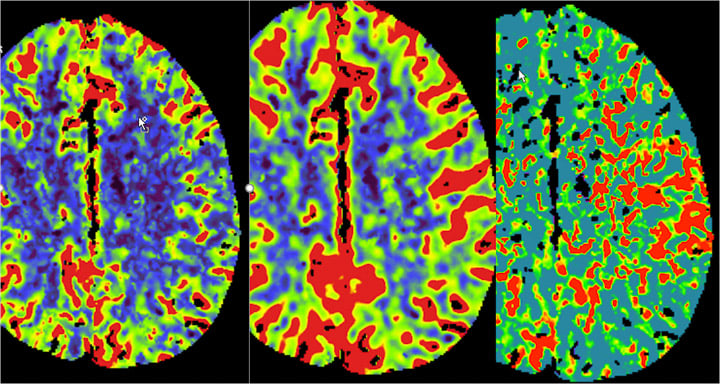

- Stroke (ischemic and hemorrhagic)

- Aneurysms, AVMs and other vascular malformations